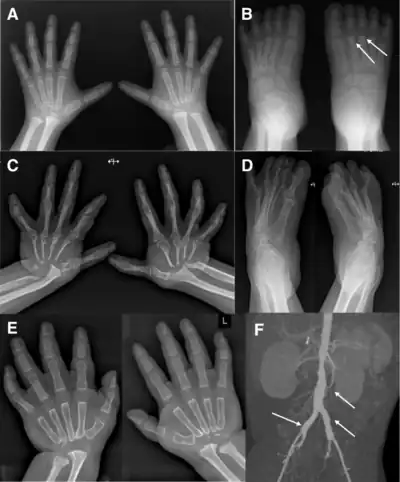

Multicentric carpotarsal osteolysis syndrome (MCTO) is a rare autosomal dominant condition.[2] This condition is also known as idiopathic multicentric osteolysis with nephropathy. It is characterised by carpal-tarsal destruction and kidney failure.

The presentation is of gradual loss of the small bones in the carpus and tarsus. This may lead to joint subluxation and instability. The kidney failure, when present, usually presents as the presence of protein in the urine.